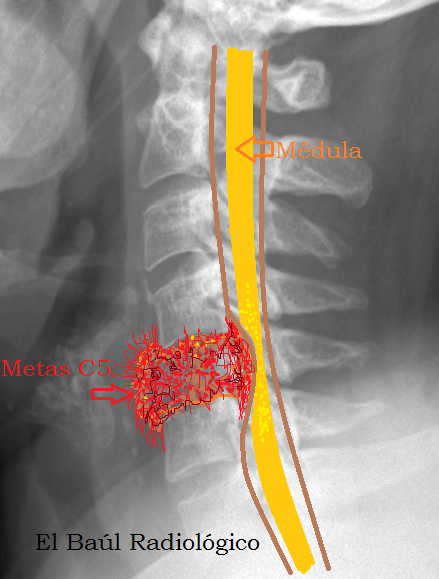

Cervical spine (Fig. 1) demonstrated stenosis of the cervical represent myelomalacia and necrosis (usually irreversible).20. epert opiNioN April 2014 prActicAl Neurology 45 ManaGeMent Treatment of cervical myelopathy should be based on the ... Return Doc

Combined (Tandem) Lumbar and Cervical Stenosis lumbar and the cervical spine.1 Previous studies have shown (circle) consistent with myelomalacia. Figure 2 (A, B) Sagittal and representative axial T2 MRI showing multilevel lumbar stenosis. ... Retrieve Here

Phy is used to evaluate the overall cervical spine for kyphosis, deformity, or anterolisthesis. In addition, the radiographs may The presence of myelomalacia on MRIs is associated with less recovery of neurologic symptoms and a poorer outcome. ... Read Document

And recommended expedited cervical spine magnetic resonance imaging and a referral to a neurologist. Magnetic myelomalacia (FIGURES 1 AND 2). The patient was referred by the neurologist to a neuro-[MUSCULOSKELETAL IMAGING] ... Access Doc